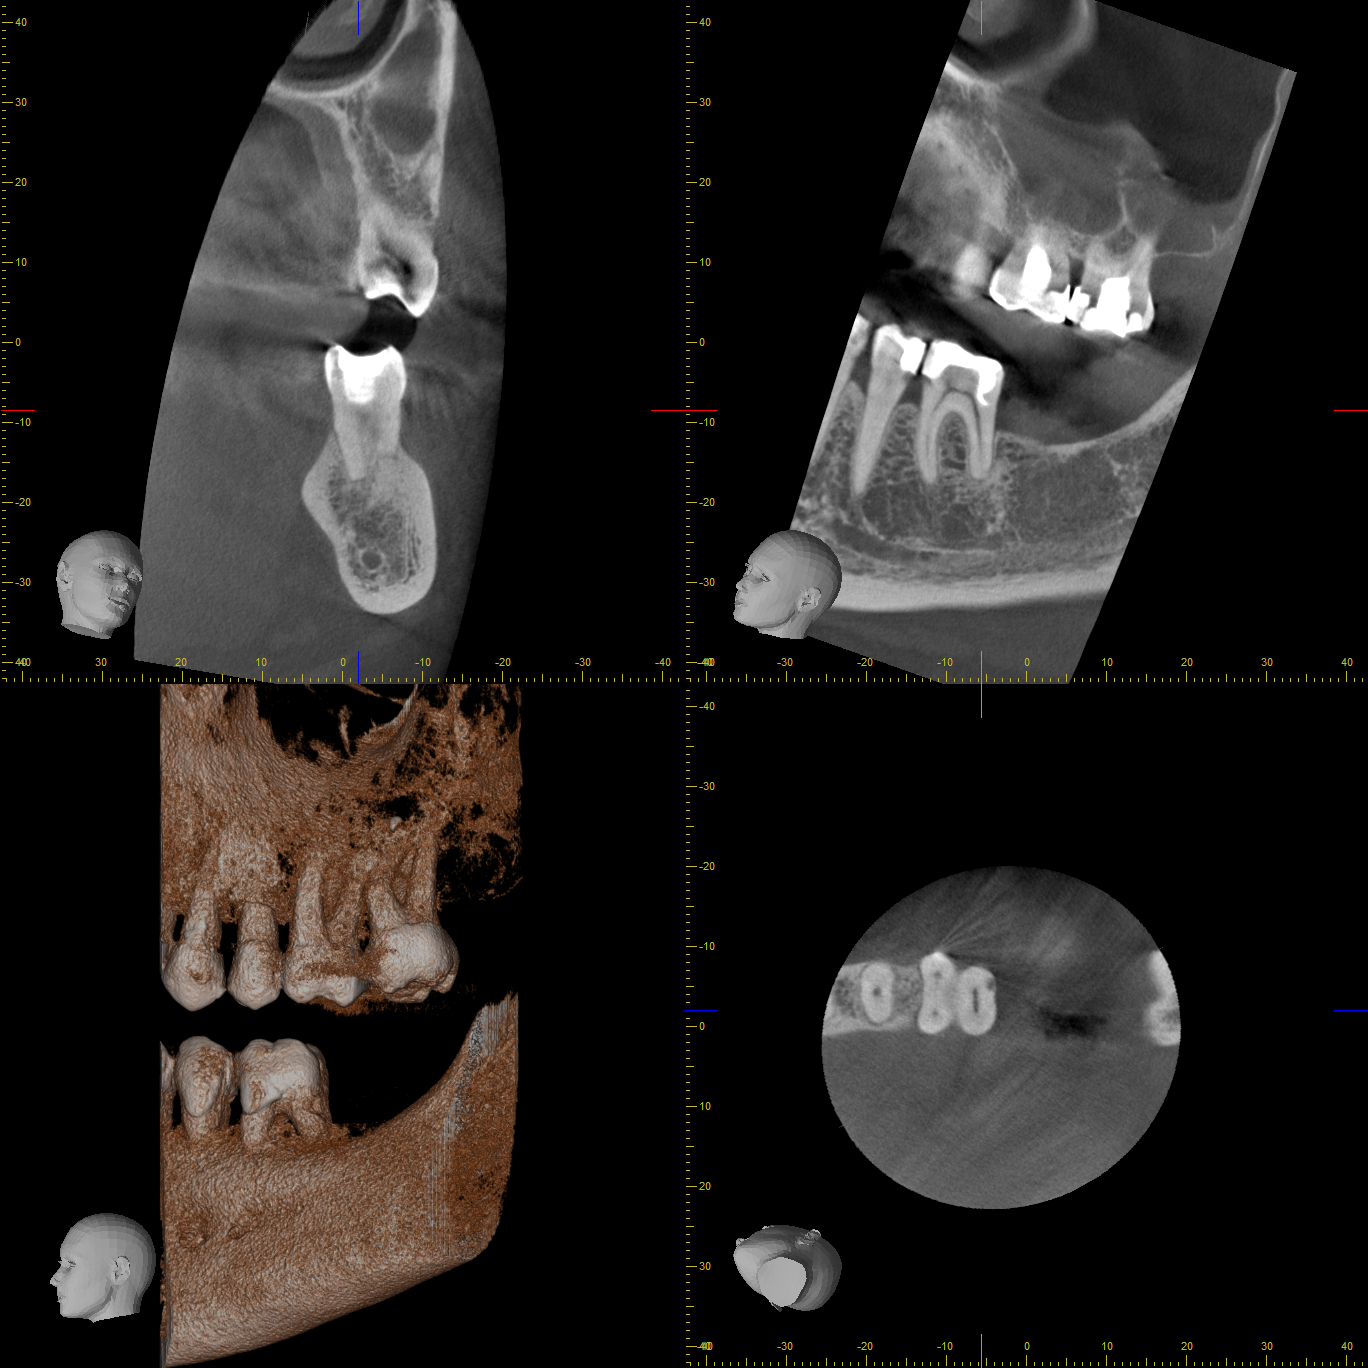

Zementoblastom